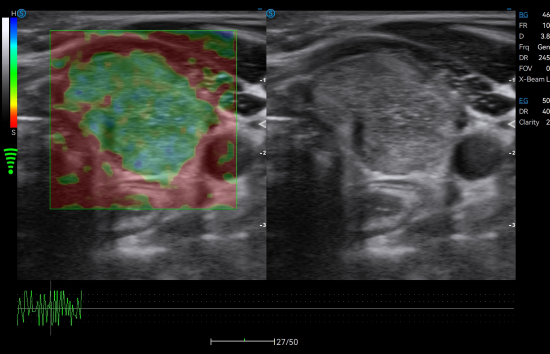

Strain Elastography distinguishes the stiffness levels of tissues in real time to detect potential abnormalities.